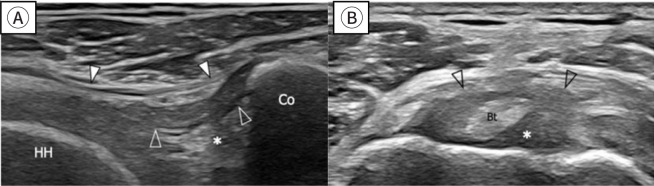

肩部疾病,包括粘连性囊炎、肩袖撕裂和肩关节骨关节炎,可严重损害老年成人患者的日常活动。本综述旨在探讨老年患者这些肩关节疾病的影像学表现,为准确诊断和有效治疗提供见解。粘连性囊炎,俗称冻肩,导致疼痛和活动受限,从而引起肩关节功能障碍。最近诊断技术的进步极大地提高了通过放射学评估诊断这种疾病的敏感性和准确性,包括MRI,磁共振关节成像(MRA)和高分辨率超声。肩袖疾病是老年人的另一个常见问题,50%-80%的病例发生全层撕裂。MRI和MRA在识别肩袖撕裂方面都是高度敏感和特异性的。此外,超声在检测冈上肌腱撕裂方面具有很高的敏感性和特异性。虽然肩关节骨关节炎不太常见,但其晚期可严重影响上肢的功能。x线平片通常是评估这类骨关节炎的首选成像技术。随着病情的恶化,CT被用于测量关节盂骨丢失、关节盂形态和关节盂倾斜度,这对于精确的手术计划至关重要。每种成像方式都有其独特的优势:x线平片用于初始结构评估,超声检查用于软组织的实时评估,MRI/MRA用于详细可视化囊和肌腱病变,CT用于精确的骨骼分析。

Shoulder diseases, including adhesive capsulitis, rotator cuff tear, and osteoarthritis of the glenohumeral joint, can significantly impair daily activities in older adult patients. This review aims to examine the radiologic findings associated with these shoulder conditions in older patients, providing insights for accurate diagnosis and effective treatment. Adhesive capsulitis, commonly known as frozen shoulder, leads to pain and restricted movement, thereby causing shoulder dysfunction. Recent advances in diagnostic technology have greatly enhanced the sensitivity and accuracy of diagnosing this condition through radiologic evaluations, including MRI, magnetic resonance arthrography (MRA), and high-resolution ultrasound. Rotator cuff disease is another frequent issue in older adults, with full-thickness tears occurring in 50%-80% of cases. Both MRI and MRA are highly sensitive and specific in identifying rotator cuff tears. Additionally, ultrasonography is recognized for its high sensitivity and specificity in detecting tears of the supraspinatus tendon. Although osteoarthritis of the glenohumeral joint is less commonly prevalent, its advanced stages can severely affect the function of the upper extremity. Plain radiography is typically the first imaging technique used to assess this type of osteoarthritis. As the condition worsens, CT is utilized to measure glenoid bone loss, glenoid version, and inclination, which are crucial for accurate surgical planning. Each imaging modality provides distinct benefits: plain radiographs for initial structural assessment, ultrasonography for real-time evaluation of soft tissues, MRI/MRA for detailed visualization of capsular and tendinous lesions, and CT for precise bony analysis.